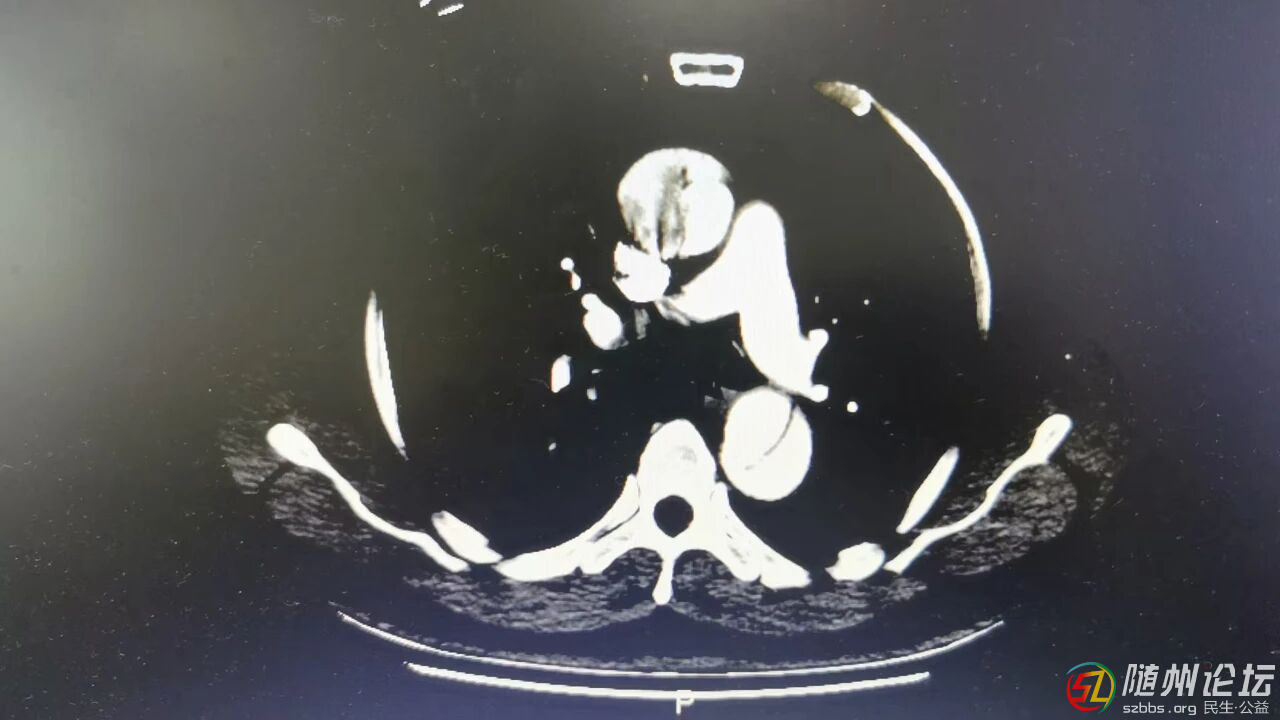

醫(yī)院急診科通過CT血管檢查,發(fā)現(xiàn)真正的元兇并非心梗,而是更為兇險(xiǎn)的“A型主動(dòng)脈夾層”,于是立即將他收治到心胸血管外科。

在做好充分準(zhǔn)備后,主任鮑傳明帶領(lǐng)科室團(tuán)隊(duì)迅速投入手術(shù)。術(shù)中發(fā)現(xiàn)情況比預(yù)想的還要危急:劉大爺?shù)纳鲃?dòng)脈已經(jīng)破裂,心包內(nèi)積血,而破口離給心臟供血的關(guān)鍵冠狀動(dòng)脈僅有不到1厘米的距離。這意味著,“炸彈”的引信已經(jīng)點(diǎn)燃,患者隨時(shí)可能心跳停止。

經(jīng)過前期的精心準(zhǔn)備,手術(shù)準(zhǔn)點(diǎn)開始。在體外循環(huán)技術(shù)支持下,手術(shù)團(tuán)隊(duì)打開患者胸腔,精準(zhǔn)定位主動(dòng)脈撕裂區(qū)域,切除病變血管段,用人工血管重建“生命主干道”,并妥善處理冠狀動(dòng)脈、頭臂動(dòng)脈等關(guān)鍵分支,確保心、腦、上肢等重要器官的供血。經(jīng)過5個(gè)多小時(shí)的持續(xù)奮戰(zhàn),團(tuán)隊(duì)拆“彈”成功,手術(shù)順利完成。目前,患者已轉(zhuǎn)至普通病房,檢查生命體征平穩(wěn),生活可以自理。